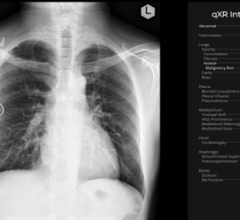

The radiology imaging channel includes technology news related to computed tomography (CT), digital radiography (DR / X-ray), ultrasound, magnetic resonance imaging (MRI), radiographic fluoroscopy (R/F), mammography, angiography, 3-D printing, contrast media injectors, molecular imaging, neurological imaging, pediatric imaging and radiation dose management.